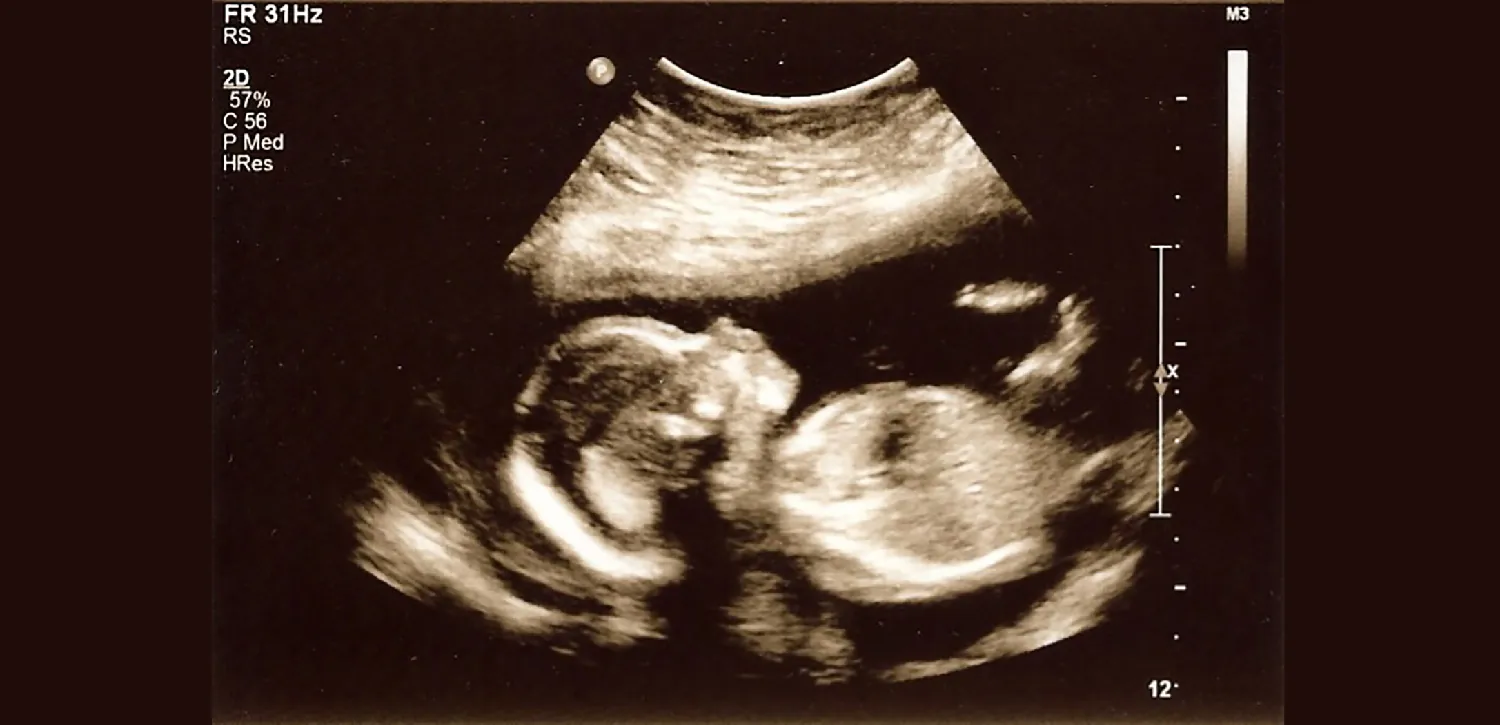

Figure 13.1 Prenatal Ultrasound Ultrasonography allows expectant parents to “see” their growing fetus. (credit: “Late second trimester ultrasound” by Robyn Alvarez/Flickr, CC BY 4.0)

Prenatal screening and diagnostic tests are recommended to provide baseline information. Ultrasound can provide information such as gestational age, congenital abnormalities, and the condition of a fetus in a high-risk pregnancy. Blood tests are used to determine blood type, Rh status, antibodies, STIs, genetic abnormalities, anemia, and gestational diabetes. Expectant parents are educated on the reasons for, and risks and benefits of, prenatal testing when deciding to have prenatal testing performed. Some prenatal tests should be performed at specific times throughout the first, second, and third trimesters. It is important that these tests are performed at the appropriate time. This chapter outlines the different types of prenatal testing for the first, second, and third trimesters.